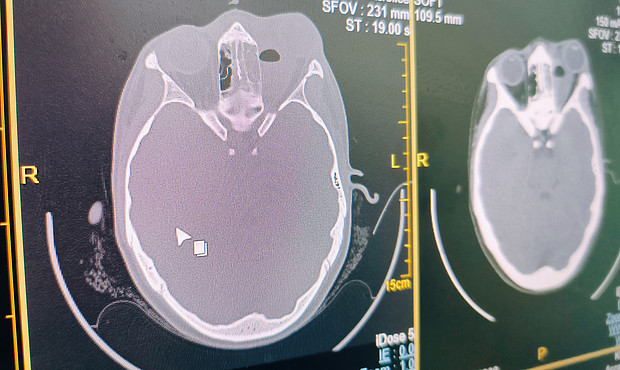

Пока оборудование используется в тестовом режиме, за первый день работы обследование прошли порядка 30 человек.